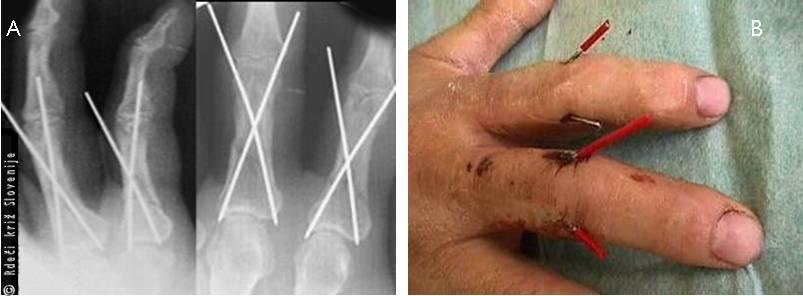

Slika 18

A, B – Zlom osnovnega členka kazalca in sredinca, osteosinteza s Kirschnerjevimi žicami.